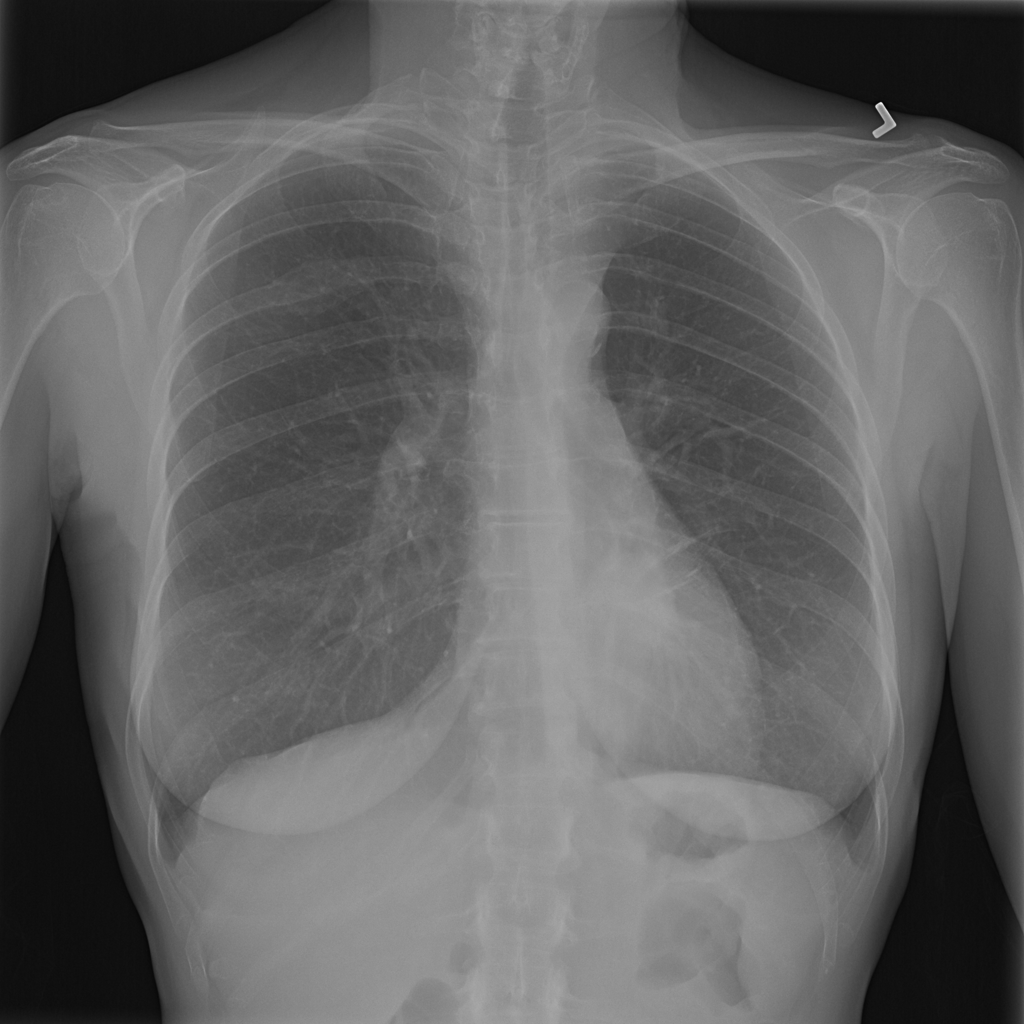

PAT-D7A5 · IMG-000Mass

PAT-D7A5 · IMG-000

PA